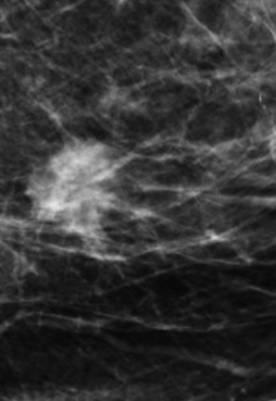

Ung thư vú

Ung thư vú - Ảnh 2

» Thông tin: Nữ giới – 72 tuổi.

» Lâm sàng: Khối tuyến vú.